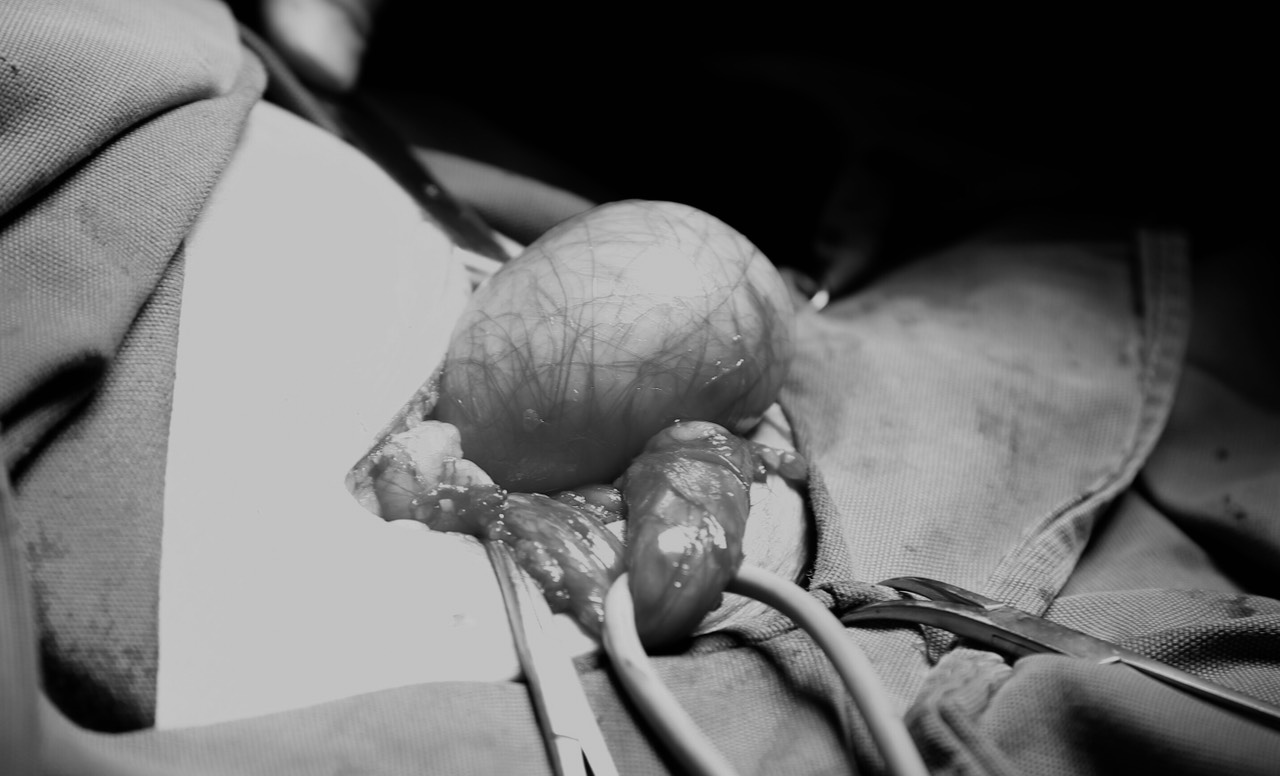

Bệnh nhân N.Đ.H, 84 tuổi, ở Hải An, Hải Phòng có tiền sử tăng huyết áp, đái tháo đường, rối loạn lipid máu, gan nhiễm mỡ độ 2, người bệnh có bụng béo mỡ, đã từng mổ thoát vị bẹn bên trái. Trước khi vào viện, người bệnh mắc rối loạn tiểu tiện, tiểu són, tiểu khó, tiểu không hết, có khối phồng to vùng bẹn phải và bìu phải, khối to dần và đau tức. Qua thăm khám, TS.BSNT Phạm Việt Hà – Giám đốc chuyên môn hệ Ngoại bệnh viện phát hiện khối của người bệnh lan xuống bìu, có dịch bên trong, cạnh tinh hoàn. Hình ảnh siêu âm và chụp cắt lớp vi tính cho thấy, hình ảnh thoát vị bẹn phải, nội dung bao thoát vị là một phần ruột non với một nửa bàng quang nằm trong bìu.

Đứng trước nguy cơ người bệnh có thể xảy ra nhiều biến chứng nguy hiểm từ việc sa bàng quang xuống bìu như: bí đái cấp, nhiễm trùng tiết niệu, túi thừa to, sỏi…, TS.BSNT Phạm Việt Hà đã quyết định tiến hành phẫu thuật cho bệnh nhân. Bên cạnh đó, trước thể trạng già yếu, nhiều bệnh lý nền kèm theo, các bác sĩ đã hội chẩn kĩ lưỡng, đảm bảo những điều kiện tốt nhất trong suốt quá trình mổ cho bệnh nhân. Sau gần 2 giờ phẫu thuật, cuộc mổ đã diễn ra thành công, ghi nhận trước, trong và sau phẫu thuật người bệnh sức khỏe ổn định, vết mổ lành tốt.